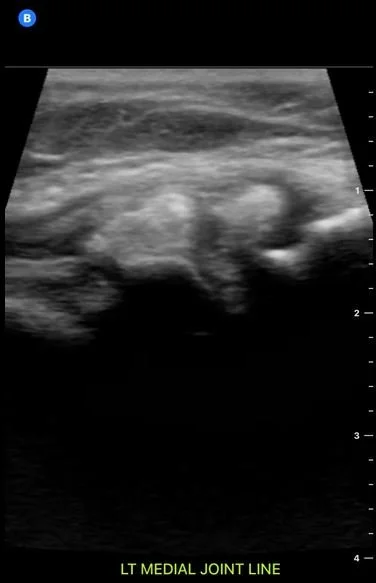

For diagnostic purposes, ultrasound offers real-time, high-resolution imaging of muscles, tendons, ligaments, joints, nerves, and other soft tissues, enabling dynamic assessment and facilitating the identification of structural abnormalities, acute injuries, and chronic overuse conditions with the advantages of portability, safety, and cost-effectiveness compared to other imaging modalities.